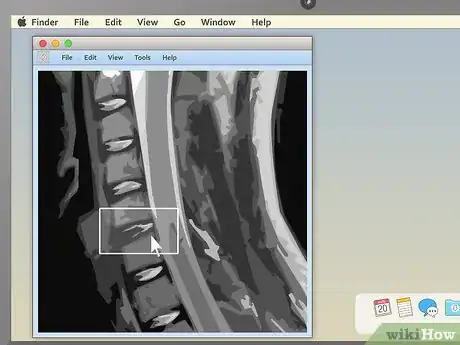

2Examine the structure of the vertebrae for spinal MRIs. MRIs of the spine are typically some of the easiest for non-doctors to read (especially in sagittal view). Look for noticeable misalignments in the vertebrae or fluid discs. Having just one of either be out of alignment (as in the example above) can be the source of serious pain.

- Behind the spinal vertebrae, in sagittal view, you'll see a white, rope-like structure. This is the spinal cord, the structure connected to all the body's nerves. Look for spots where the vertebrae or discs seem to "pinch" or press into the spinal cord — because the nerves are so sensitive, just a little pressure can lead to pain.